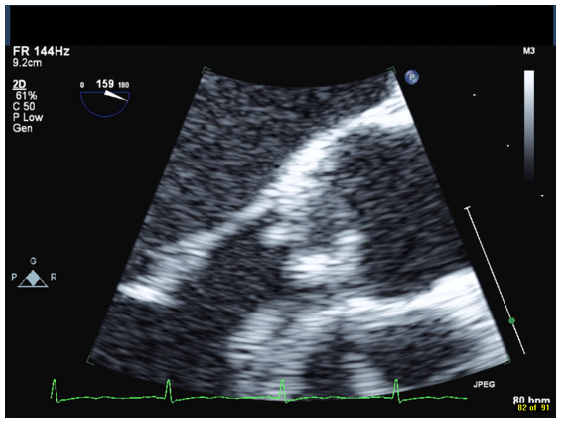

A 42-year-old male with a history of chronic nephrolithiasis presented to the hospital after neighbors found him unconscious at home. On initial evaluation, he was febrile (38.9) with blood pressure of 120/104mmHg. He was severely hypoxic with a sinus rate of 90 beats/minute. His examination revealed multiple abrasions, and he was minimally responsive with a holosystolic murmur at the apex. His electrocardiogram showed normal sinus rhythm with no acute ST-T wave changes. Laboratory data revealed a white cell count of 17.4/nl, platelet count of 109/nl, lactate level of 4.8 mmol/l and creatinine of 1.57mg/dl. Computed tomography of the head revealed multiple regions of acute infarction involving the right inferior cerebellum, left occipital lobe with mass effect on the left occipital horn. He underwent a transthoracic echocardiogram that showed vegetations on both the mitral and aortic valve. He underwent a trans-esophageal echocardiogram, which demonstrated multiple vegetations on the mitral (Figure 1), aortic (Figure 2) and pulmonic valves (Figure 3) with severe pulmonic, mitral and aortic insufficiency (Figure 4 & 5). Despite negative urine cultures, serial blood cultures grew Aerococcus urinae and he was given appropriate IV antibiotics. He was evaluated for possible valvular surgery and was deemed to be a poor surgical candidate. He later developed splenic and renal infarcts followed by significant hemodynamic instability requiring vasopressors and ultimately succumbed to his illness after he developed multi organ failure and disseminated intravascular coagulation.